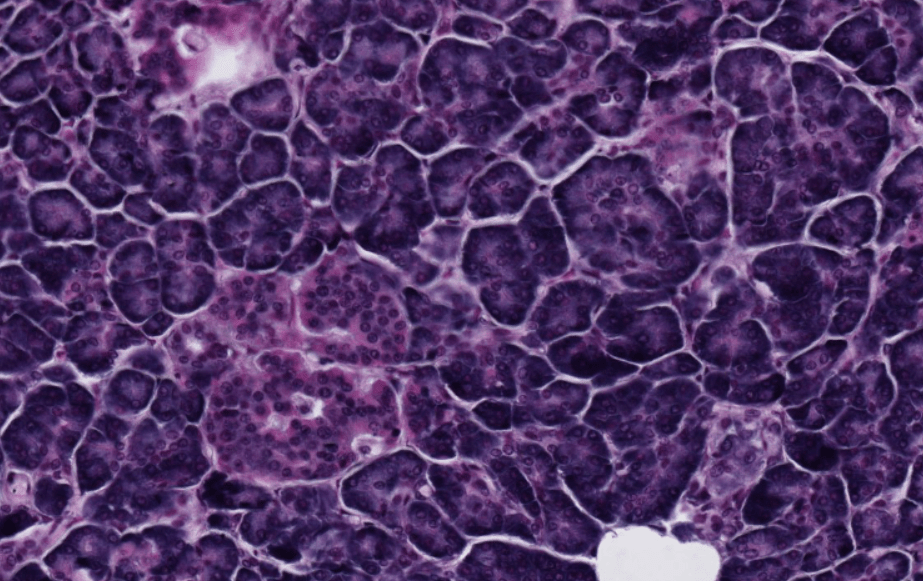

SEBÁCEAS

Su mecanismo de secreción es holocrino.

Asociadas a folículos pilosos.

Su secreción principal es sebo y este desaperec durante la técnica histológica, por eso se ve «pálido» con HyE.

Se ubican en casi toda la piel excepto piel gruesa.